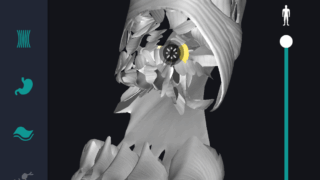

はじめに 本記事では、人体解剖学における専門的な部位の知識を始めに、効果的な勉強法についてご説明します。 人体解剖学では様々な器官や筋肉、骨の名称を覚えるだけではなく、体のどの位置に存在するのかまで覚えなければなりません。そのため、できるだ...